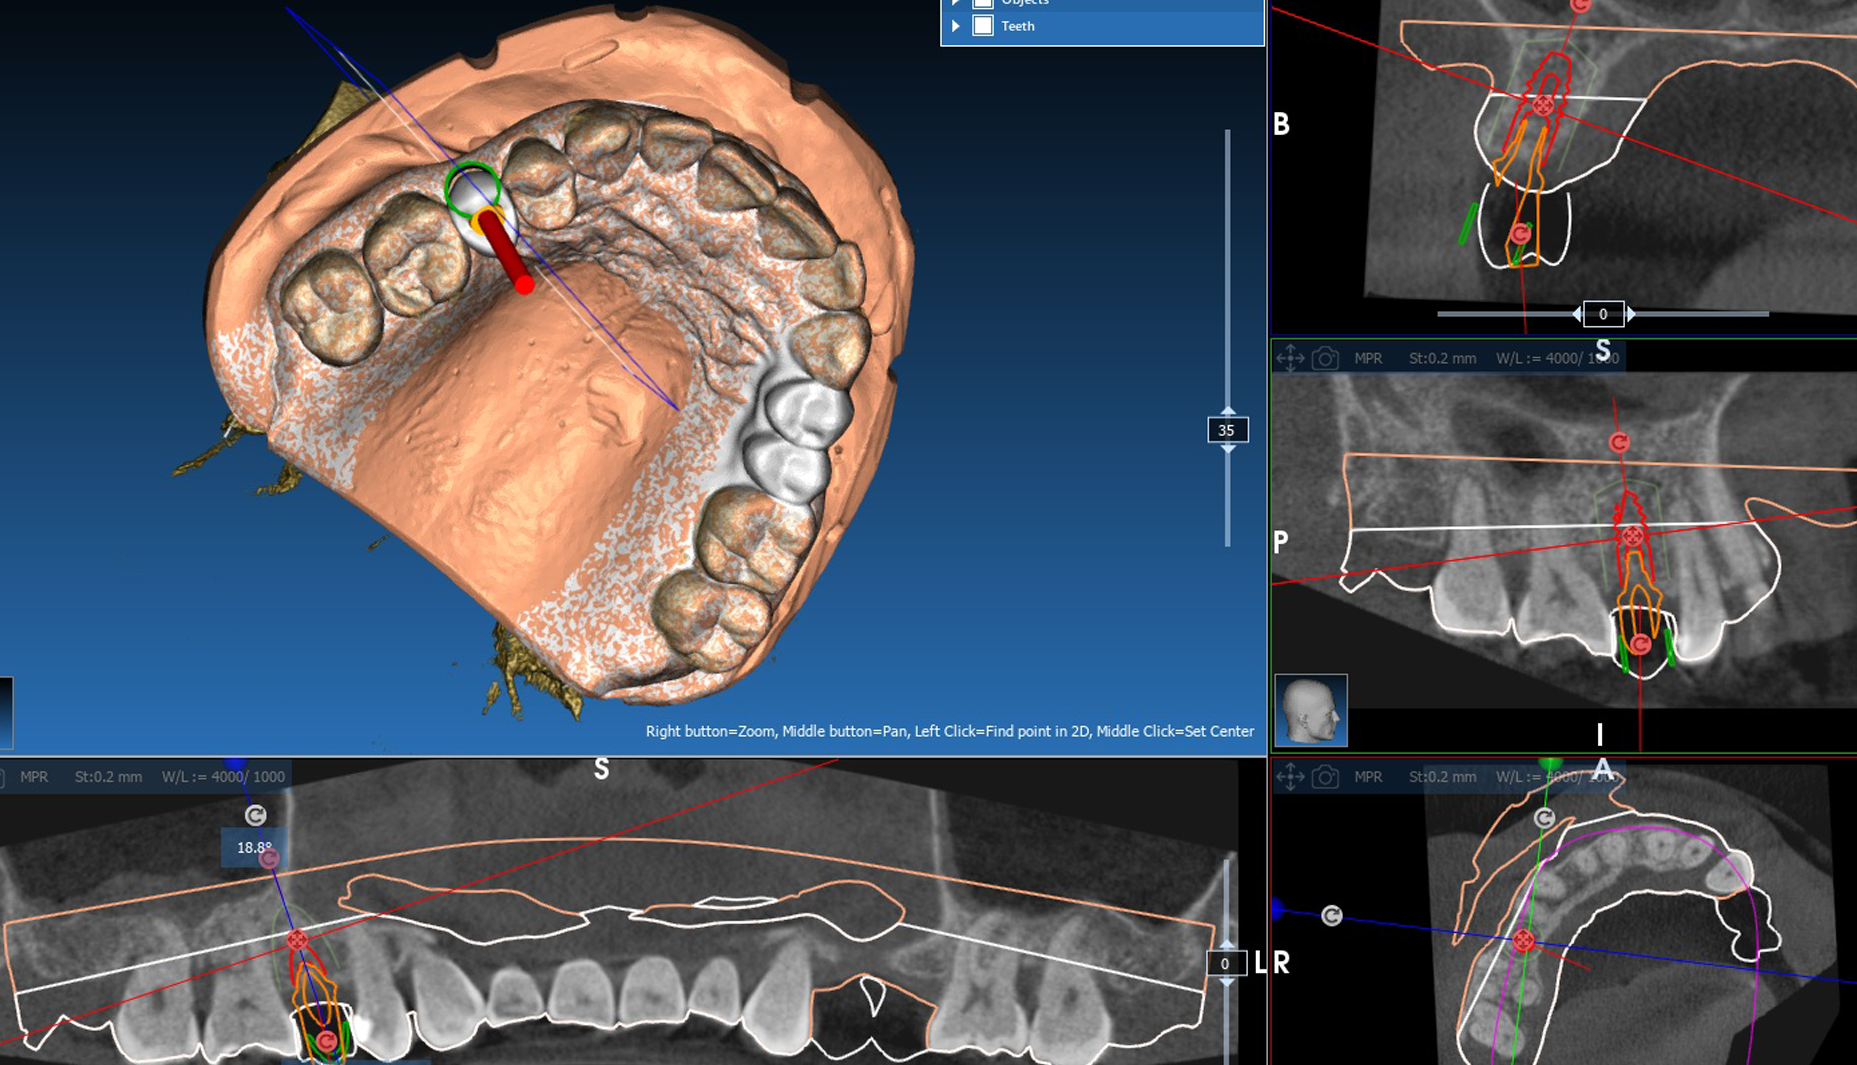

X-ray diagnostics and planning

A Dicom 3.0 file is created with the double scan technique (CT/DVT). Likewise, the current scon prosthesis alone is recorded and digitised In the case of residually toothed, not heavily restored jaws the double scan technique can be dispensed with.

The data thus obtained is then read into the ICХ-МАGELLAN 3D planning software. When the planning of the implant positions in the 3D software is completed, the data for setting the positioner iscalculated.

The following safety distances must be observed:

• 3.0 mm to the adjacent implant.

• Implant diameter and length must be determined so that there is sufficient bone (at least 1.0 mm) around the implant

• 2.0 mm to the mandibular nerve or inferior alveolar nerve.

• 15 mm to the adjacent natural tooth.